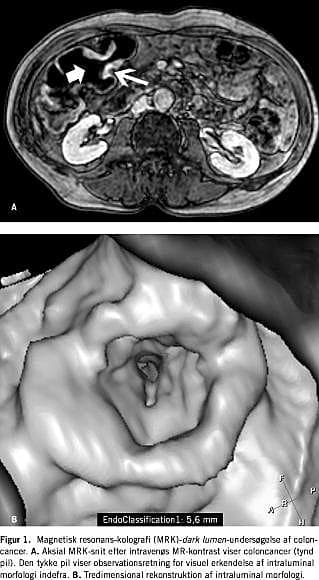

Udviklingen af kraftigere computere og MR-skannere har gjort det klinisk muligt at undersøge hele colon ved hjælp af MRK. Primære undersøgelser tyder på, at MRK er egnet til påvisning af kolorektale tumorer (polypper eller cancer) (Figur 1 ) og diagnostik af inflammatorisk tarmsygdom (IBD) (Figur 2 ).

Virtuel koloskopi

Intraluminal morfologi kan undersøges med »virtuel koloskopi«-datarekonstruktion [23]. Ved hjælp af computerteknologi kan billederne omdannes til tredimensionelle billeder, således at tarmens overflade kan gennemses som ved en »almindelig« koloskopi. Metoden giver et billede, der ligner det optiske billede i et endoskop.